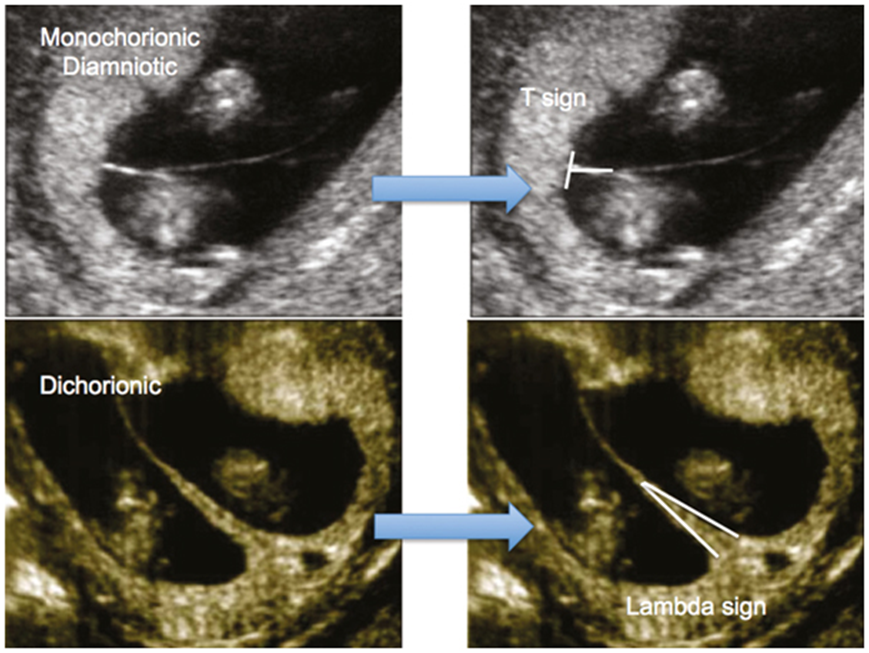

- இரட்டையர்கள் டைகோரியானிக் டயம்னியோடிக் ஆக இருக்கலாம். இரட்டையர்களுக்கு தனித்தனி அம்னியன்கள் மற்றும் கோரியான்கள் உள்ளன. இதுகுறைந்த ஆபத்துள்ள இரட்டைகர்ப்பத்தின் வகை.

- இரட்டையர்கள் மோனோ கோரியோனிக்டயம்னியோடிக் ஆக இருக்கலாம். இரட்டையர்கள் ஒரேகோரியன் மற்றும் நஞ்சுக்கொடியைப்பகிர்ந்து கொள்கிறார்கள். அவைதனித்தனி அம்னோடிக்பைகளில் வளரும்.

ஒன்றுக்கு மேற்பட்ட கர்ப்பங்களில் செய்யப்படும்ஸ் கேன்வகைகள்:

- டேட்டிங்ஸ்கேன் மற்றும் ஒருங்கிணைந்த ஸ்கிரீனிங் சோதனையின் அதேநேரத்தில் ஒரு கோரியானிசிட்டிஸ்கேன். குழந்தைகள் நஞ்சுக்கொடியைப்பகிர்ந்துகொள்கிறார்களா அல்லது ஒன்று உள்ளதா என்பதை இதுசரிபார்க்க வேண்டும்.

- சிக்கலற்ற மோனோகோரியோனிக் டயம்னியோடிக் இரட்டைக்கர்ப்பங்களைக்கொண்ட தாய்மார்கள் 16 வது வாரத்திலிருந்து ஒவ்வொரு 2 வாரங்களுக்கும் ஸ்கேன் செய்யப்பட வேண்டும்.

- கருவுற்ற 16 முதல் 24 வாரங்கள்வரை TTTS நோயைக்கண்டறிய மோனோகோரியோனிக் இரட்டையர்கள் பதினைந்துநாட்களுக்கு ஒருமுறை ஸ்கேன் செய்யப்பட வேண்டும்.